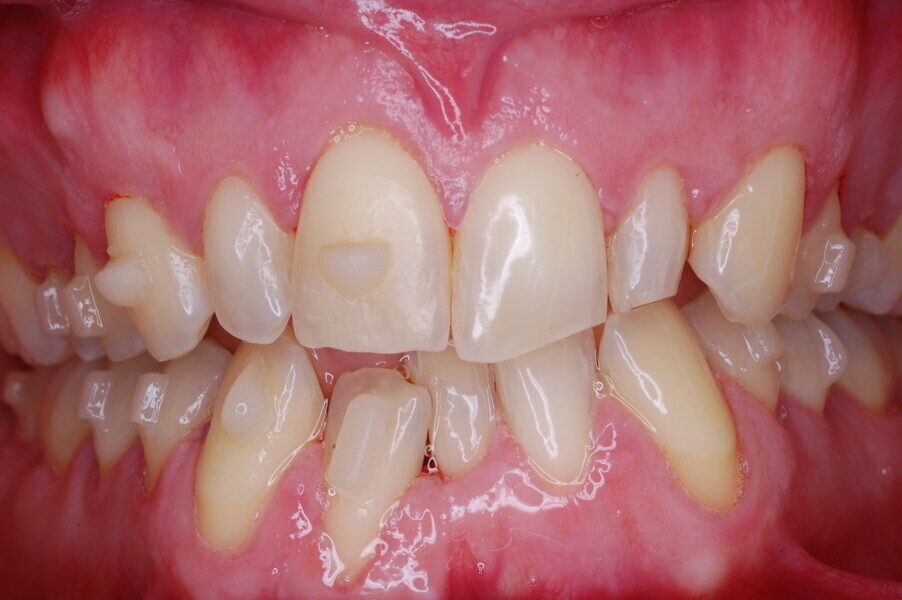

A healthy 39-year-old man presented to our orthodontic office with the chief complaint of an unattractive dental appearance and fear of the orthognathic surgery proposed by another orthodontist. Clinically, the patient’s profile was straight, and the frontal view did not show any facial asymmetry. The functional examination did not reveal any mandibular deviation or reduced movements. The patient had no joint pain, and no joint noise was observed.

Figs. 1–8: Pretreatment facial and intra-oral photographs.

From the periodontal point of view, the patient showed a good attitude to oral hygiene, but crowding of the mandibular incisors made cleaning difficult in that area, causing plaque accumulation and localised gingival inflammation. The panoramic radiograph revealed the presence of the mandibular third molars and confirmed the absence of the mandibular right central incisor (Fig. 10).

The cephalometric analysis showed a skeletal Class II malocclusion (convexity of Point A: 4.9 mm), a slightly retruded chin position (facial depth: 78.1°) and a skeletal open bite tendency (lower facial height: 53.19°; facial axis: 80.58°; Fig. 9). The mandibular incisors were lingually tipped (Li–APog: 9.3°) and retruded (Li–APog: 1.55 mm), and there was an increased inter-incisal angle of 142.9°.